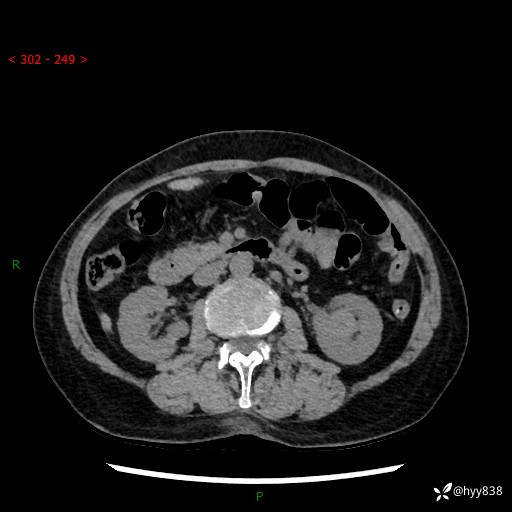

72岁/女,检查发现左肾占位1天。为了满足诊断,常规四期后,又加了延迟期-结果公布~

【患者信息】:72岁/女

【主诉】:检查发现左肾占位1天

【现病史及既往史】:患者于1天前检查发现左肾占位,无畏寒发热,无咳嗽咳痰,无腰腹部疼痛不适,无肉眼血尿、无尿频尿急症状,起病来,患者未行特殊治疗,为求进一步诊治,门诊以"左肾占位"收治入院。 发病来患者精神、饮食、睡眠良好,小便如上,大便正常,体重无明显变化。

【检查】:肾脏CT平扫+增强